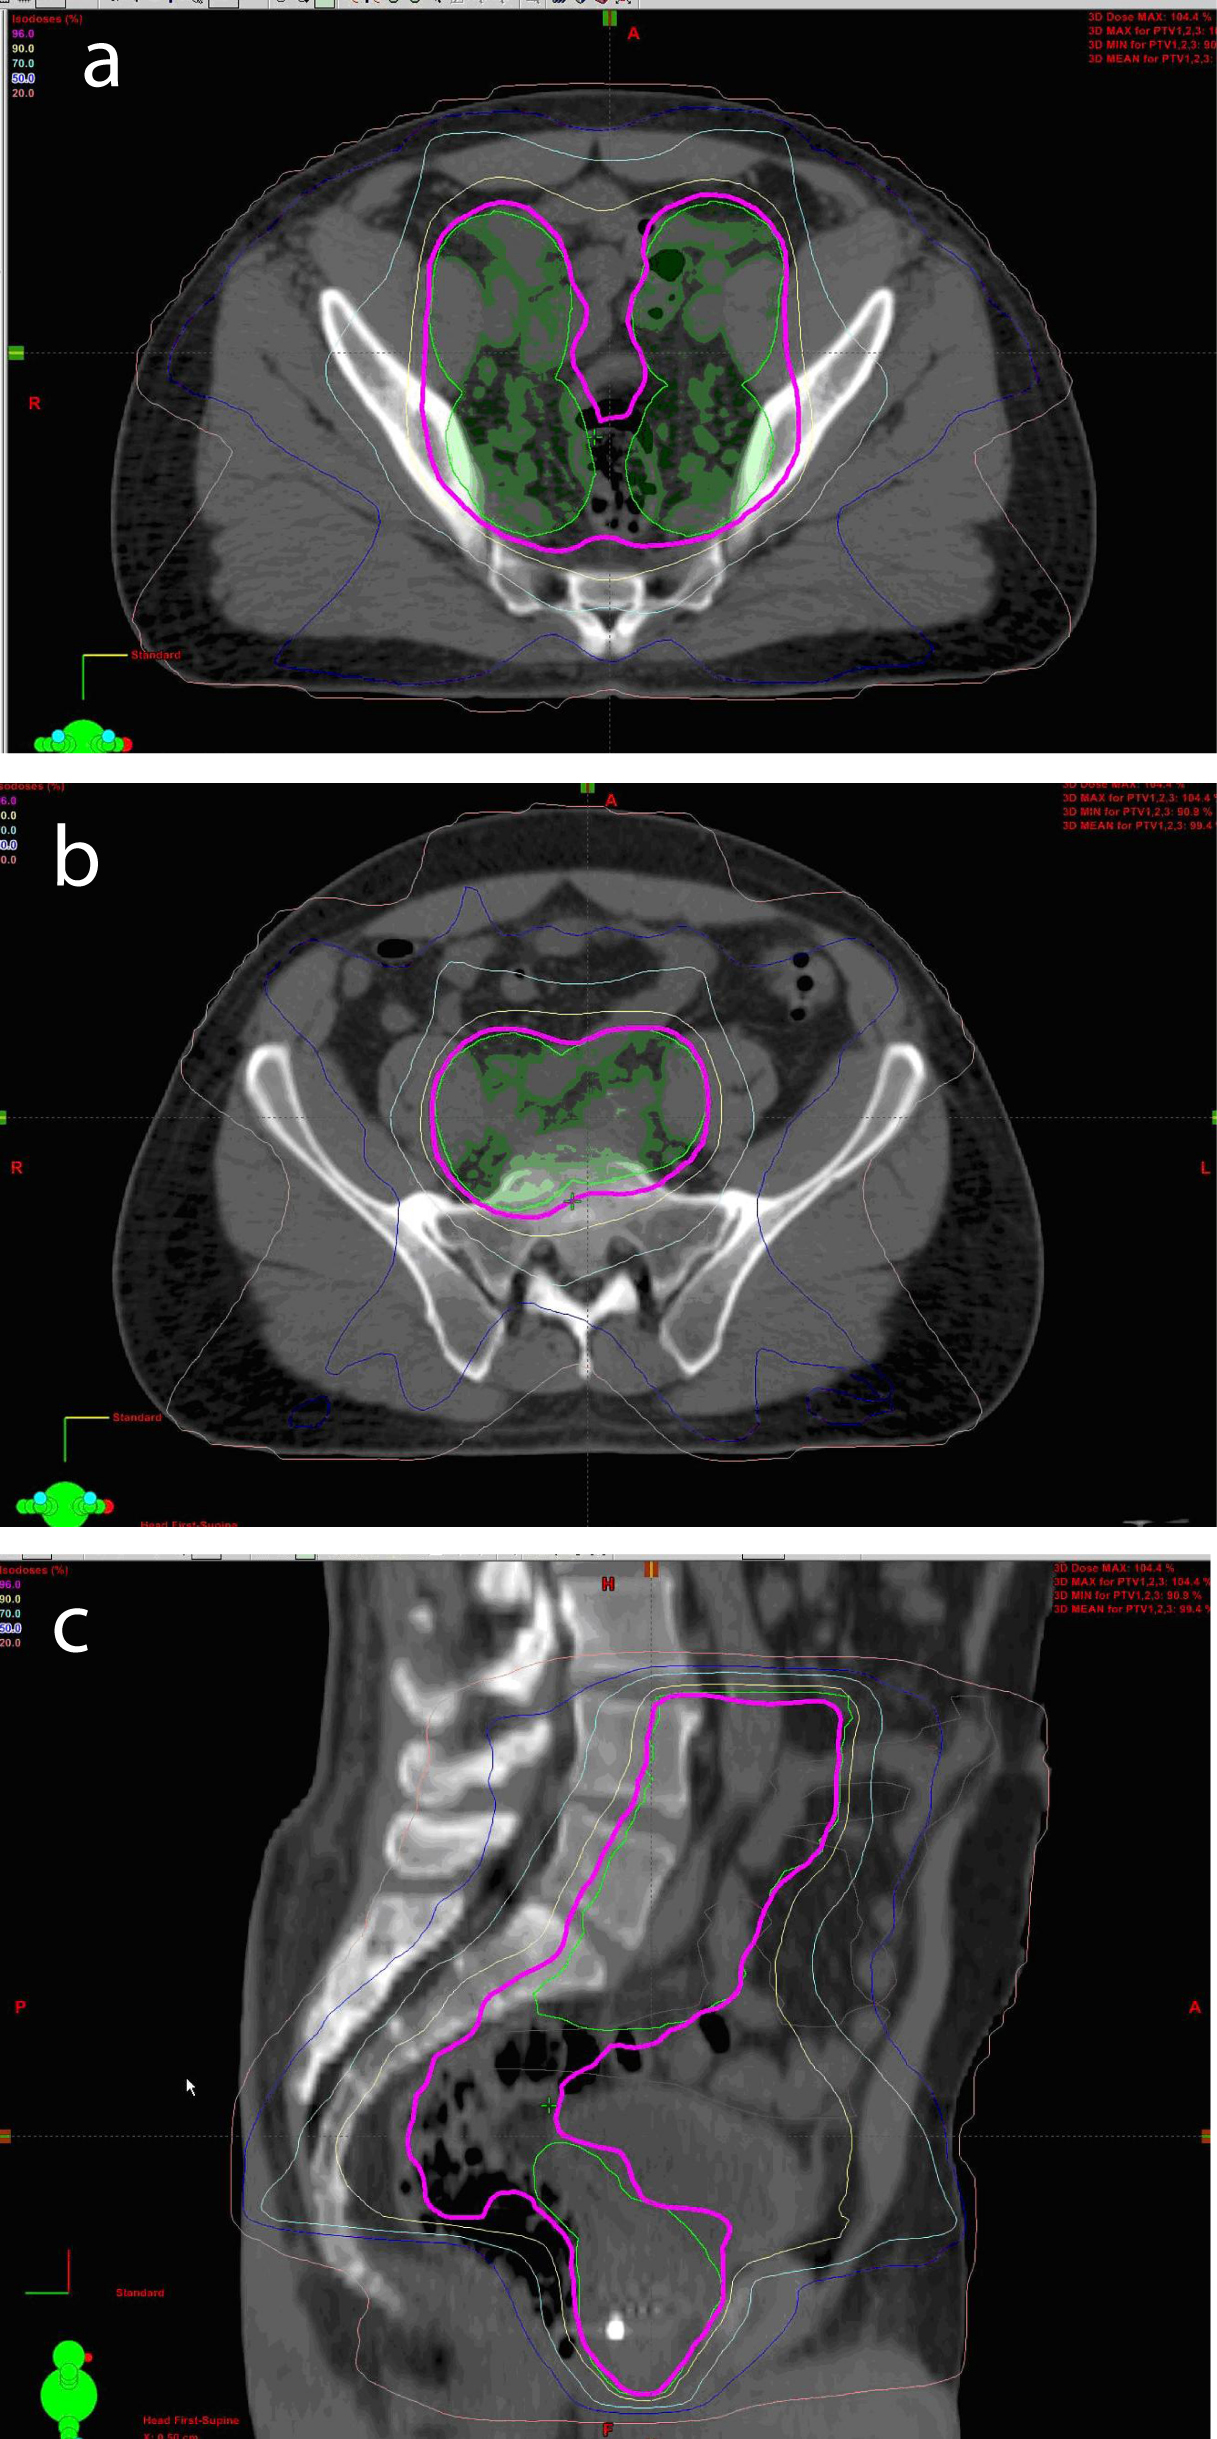

All patients were able to complete the full course of treatment and were followed closely, one patient was take off the protocol as he subsequently moved out of country and was unable to be followed as per the predetermined schedule (Fig. 1).

![]() Click for large image | Figure 1. Axial View of Conformal IMRT Isodoses in Pelvis (a, b). Sagittal View of Conformal IMRT Isodoses in Pelvis (c) |